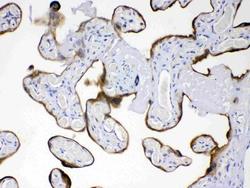

- Main image

- Experimental details

- Western blot analysis of AMFR expression in rat thymus extract (lane 1) and HELA whole cell lysates (lane 2). AMFR at 78KD was detected using rabbit anti- AMFR Antigen Affinity purified polyclonal antibody (Catalog # PB10039) at 0.5 μg/mL. The blot was developed using chemiluminescence (ECL) method (Catalog # EK1002).

- Additional image